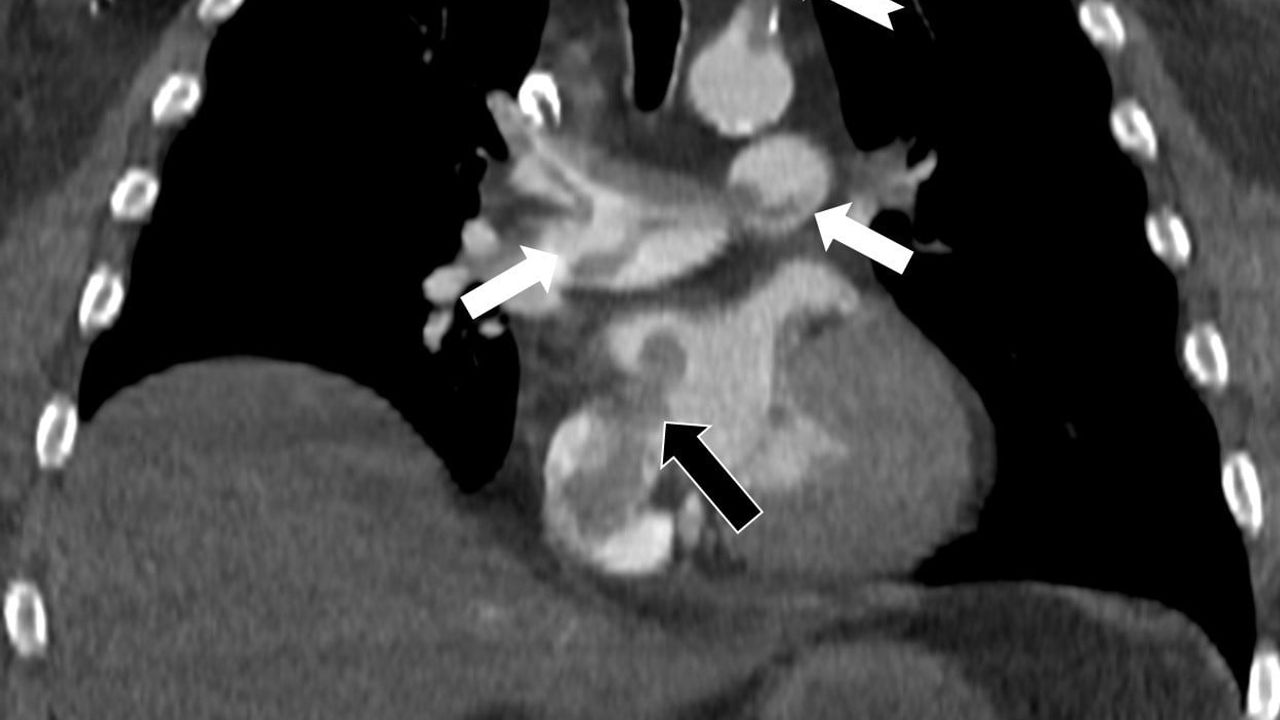

Çalışmada sunulan olguda, 60 yaşındaki bir hasta, penis ameliyatından 5 gün sonra ani göğüs ağrısı, nefes darlığı ve kol uyuşması şikâyetleriyle hastaneye başvurdu. Yapılan bilgisayarlı tomografi anjiyografisi incelemesi, toplar damarlardan kaynaklanan pıhtının akciğer damarlarını tıkadığını gösterdi. Aynı zamanda görüntüleme, pıhtının kalpte daha önce fark edilmemiş bir delikten (atriyal septal defekt) geçerek sağdan sola yönelip ana atardamara ulaşması ve sol kol damarını tıkaması bulgusunu ortaya koydu.

Prof. Dr. Karabulut’un çalışması, bacak damarlarından kaynaklanan pıhtıların yalnızca akciğer embolisine yol açmakla kalmayıp; kalp deliği varlığında ana atardamar yolu aracılığıyla beyin, kol ve bacak gibi bölgelere geçerek ani damar tıkanmasına (paradoks emboli) neden olabileceğini vurguluyor. Çalışmada, nedeni bilinmeyen pıhtı atmalarında kalpteki gizli deliklerin mutlaka araştırılması gerektiği belirtildi.

Makale, ekokardiyografi ve bilgisayarlı tomografi tetkiklerinin erken ve doğru tanı koymada hayat kurtarıcı rol oynadığını işaret ediyor; çalışmada bu görüntüleme yöntemlerinin birlikte kullanılmasının kritik olduğu vurgulanıyor.